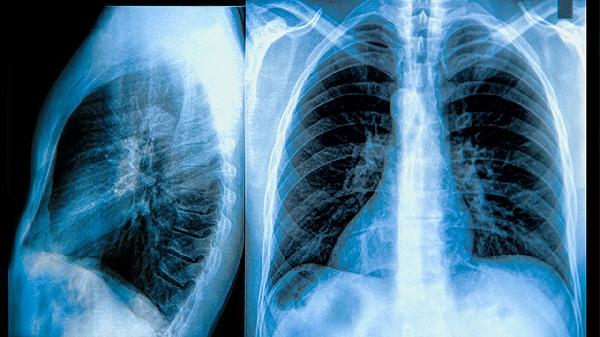

對于藥物治療效果不佳的嚴(yán)重患者,可考慮手術(shù)治療。常見手術(shù)方式包括肺減容術(shù)和肺移植術(shù)。肺減容術(shù)適用于肺氣腫患者,可以改善肺功能;肺移植適用于終末期肺病患者。手術(shù)治療風(fēng)險(xiǎn)較大,需要嚴(yán)格評估手術(shù)適應(yīng)癥和禁忌癥。